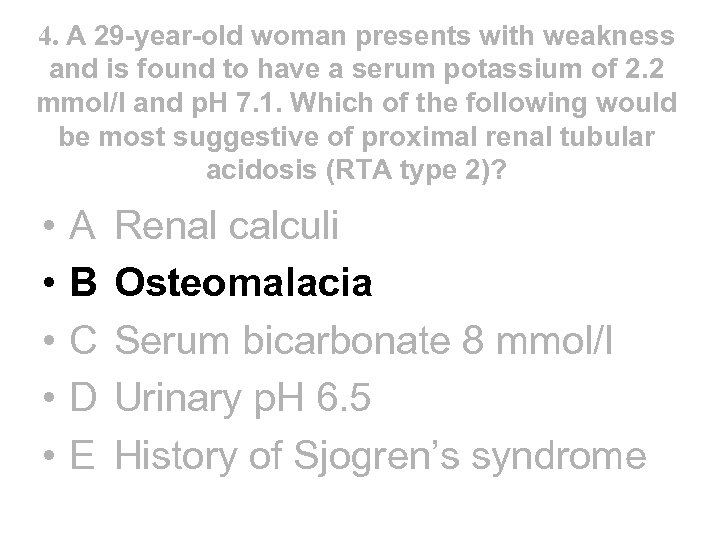

4. A 29 -year-old woman presents with weakness and is found to have a serum potassium of 2. 2 mmol/l and p. H 7. 1. Which of the following would be most suggestive of proximal renal tubular acidosis (RTA type 2)? • • • A B C D E Renal calculi Osteomalacia Serum bicarbonate 8 mmol/l Urinary p. H 6. 5 History of Sjogren’s syndrome

4. A 29 -year-old woman presents with weakness and is found to have a serum potassium of 2. 2 mmol/l and p. H 7. 1. Which of the following would be most suggestive of proximal renal tubular acidosis (RTA type 2)? • • • A B C D E Renal calculi Osteomalacia Serum bicarbonate 8 mmol/l Urinary p. H 6. 5 History of Sjogren’s syndrome

4. A 29 -year-old woman presents with weakness and is found to have a serum potassium of 2. 2 mmol/l and p. H 7. 1. Which of the following would be most suggestive of proximal renal tubular acidosis (RTA type 2)? • • • A B C D E Renal calculi Osteomalacia Serum bicarbonate 8 mmol/l Urinary p. H 6. 5 History of Sjogren’s syndrome

4. A 29 -year-old woman presents with weakness and is found to have a serum potassium of 2. 2 mmol/l and p. H 7. 1. Which of the following would be most suggestive of proximal renal tubular acidosis (RTA type 2)? • • • A B C D E Renal calculi Osteomalacia Serum bicarbonate 8 mmol/l Urinary p. H 6. 5 History of Sjogren’s syndrome

What can go wrong? Type 2 - Proximal RTA due to failure of bicarbonate reabsorption (uncommon in adults) Type 1 - Distal RTA due to failure of acid secretion (common) Type 3 - Poorly characterised mix of types 1 and 2 (vanishingly rare) Type 4 - Hyporeninaemic hypoaldosteronism causing acidosis and hyperkalaemia (common)

What can go wrong? Type 2 - Proximal RTA due to failure of bicarbonate reabsorption (uncommon in adults) Type 1 - Distal RTA due to failure of acid secretion (common) Type 3 - Poorly characterised mix of types 1 and 2 (vanishingly rare) Type 4 - Hyporeninaemic hypoaldosteronism causing acidosis and hyperkalaemia (common)

Renal tubular acidosis • Distal - type 1 • Proximal - type 2 • rare Frequency • common Mechanism • failure to excrete H+ • failure to reabsorb bicarbonate • 1 y or 2 y to cystinosis, • 1 y or 2 y to SLE, Causes wilsons, myeloma, sjogrens, PBC, sjogrens - often assoc CAH, urinary with failure to reabsorb obstruction, PO 4, AA, glucose, urate medullary sponge, (fanconi) lithium

Renal tubular acidosis • Distal - type 1 • Proximal - type 2 • rare Frequency • common Mechanism • failure to excrete H+ • failure to reabsorb bicarbonate • 1 y or 2 y to cystinosis, • 1 y or 2 y to SLE, Causes wilsons, myeloma, sjogrens, PBC, sjogrens - often assoc CAH, urinary with failure to reabsorb obstruction, PO 4, AA, glucose, urate medullary sponge, (fanconi) lithium

Renal tubular acidosis • Distal - type 1 Urine p. H • • Serum bic • Serum K Complications • Therapy p. H > 5. 5 often < 10 mmol/l usually low nephrocalcinosis, stones • low dose bicarbonate, K supps, citrate to stop Ca-PO 4 deposition if stone former

Renal tubular acidosis • Distal - type 1 Urine p. H • • Serum bic • Serum K Complications • Therapy p. H > 5. 5 often < 10 mmol/l usually low nephrocalcinosis, stones • low dose bicarbonate, K supps, citrate to stop Ca-PO 4 deposition if stone former

Renal tubular acidosis • Distal - type 1 Urine p. H • • Serum bic • Serum K Complications • Therapy • Proximal - type 2 p. H > 5. 5 • often < 10 mmol/l • usually low • nephrocalcinosis, • stones • low dose bicarbonate, • K supps, citrate to stop Ca-PO 4 deposition if stone former Variable* 14 -20 mmol/l* normal or low osteomalacia, rickets (not calcinosis or stones) high dose bicarbonate *when serum bicarb drops below a threshold level in type 2 RTA, the tubules start reabsorbing bicarbonate which means serum bic can be higher and urine p. H lower than in type 1 - known as the “threshold effect”